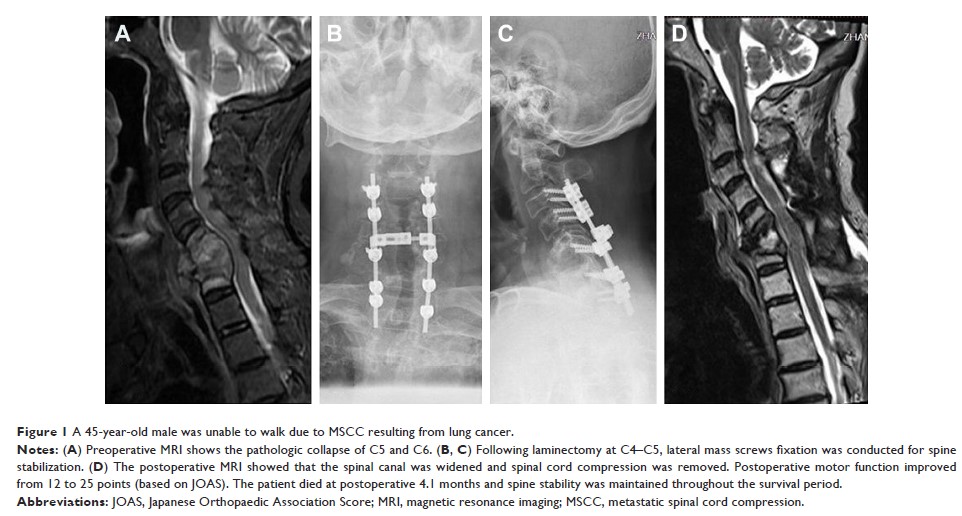

Case Series

- 作者:Mingxing Lei, Jun Yu, Shiju Yan, Xiao An, Yaosheng Liu

- 期刊:Therapeutics and Clinical Risk Management